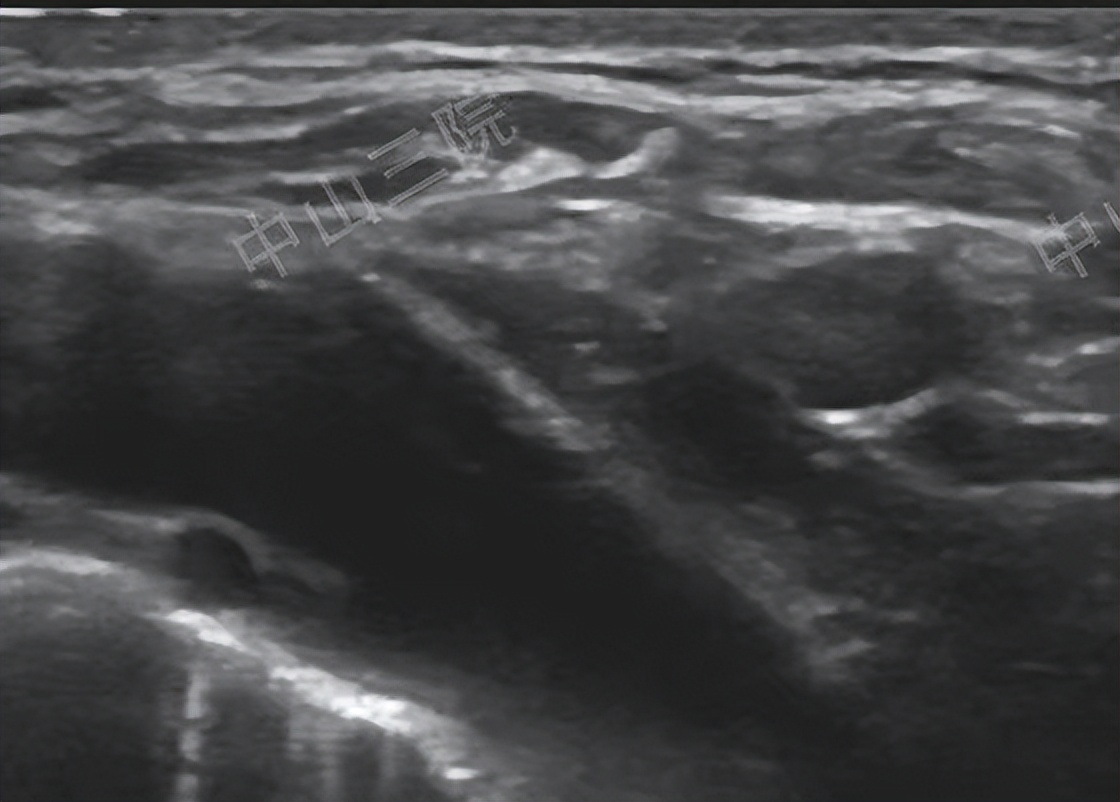

甲状腺癌热消融治疗无创、安全、简便,术后三年复查一切正常

她怀着试一试的心情找到了中山大学附属第三医院超声科的任杰教授,任教授先为欧女士做了详细的术前检查,结果显示只有右侧锁骨上窝的一枚淋巴结转移病灶,病灶局限,符合热消融治疗的适应证。皮肤上进行局麻后,欧女士清晰地感受到一根针穿入皮肤,不到一个小时,任教授说手术结束,她如此惊讶,没有明显的不适,没有剧痛,一切结束了!

第二天鸥女士出院了,没有神经损伤,没有声音嘶哑,她感到一身轻松。可是,会不会又复发,鸥女士没有放松,乖乖的按照医生叮嘱,每半年复查一次。一年,那个淋巴结转移灶消失不见了,而且抽血指标也显示没有复发;第二年,没有异常;这次,可是第三年了,复查结束,当任教授告诉她,没有看到复发灶,抽血指标也正常时,她松了一口气,嘴角微微上扬起来。